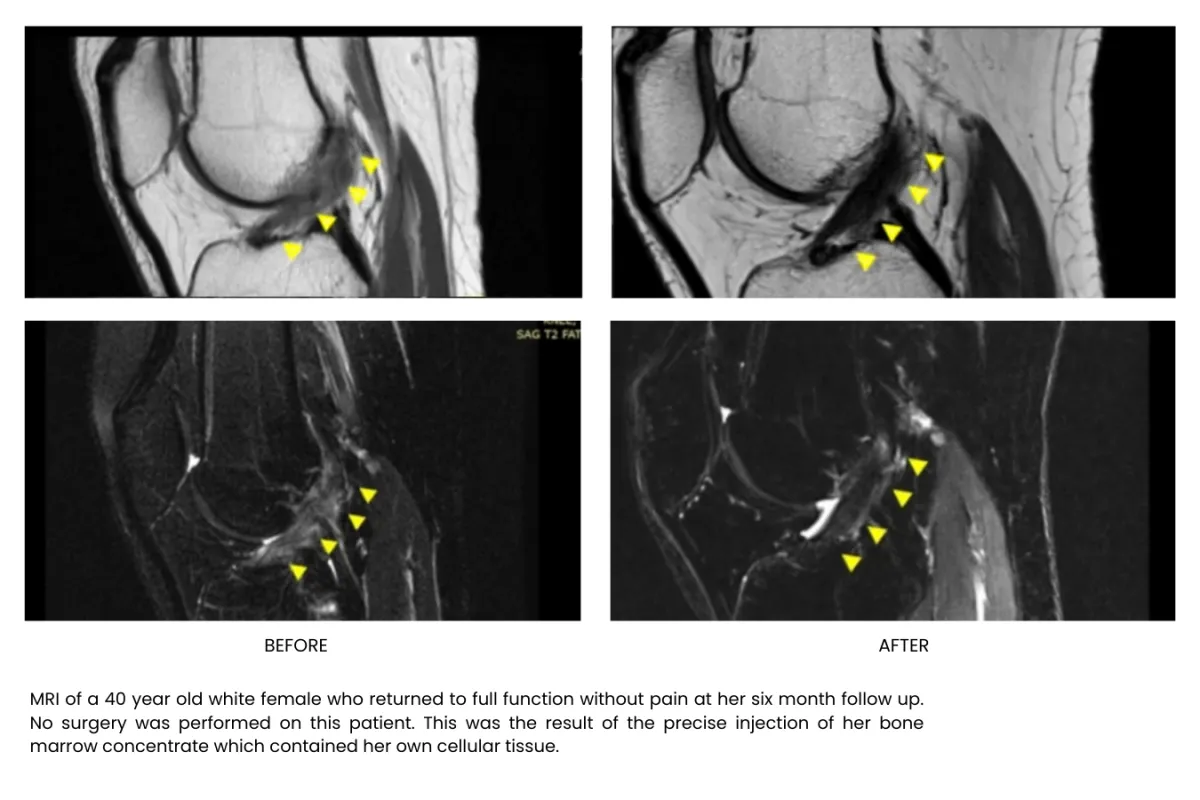

Millions of stem cells delivered precisely in the injured area building up tissue, recovering and freeing your from pain, without surgery or long recoveries.